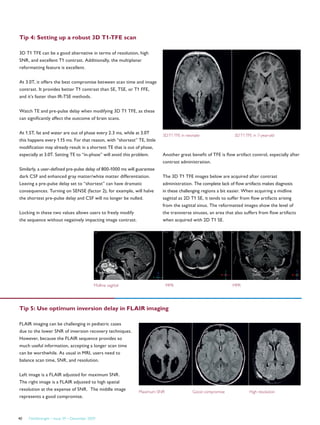

enjoying the more relaxing atmosphere of

the Philips Panorama MRI system with

Ambient Lighting.

Ambient Lighting increases patient

comfort

Under standard examination room lighting,

patients may feel vulnerable, exposed and

anxious. Installation of Ambient Lighting

MR along the perimeter of the room,

creates a more soothing and relaxing

atmosphere. Walls are washed by warm

inviting hues of red, green, yellow and blue,

calming patients and providing a source of

positive distraction. Furthermore, patients

can actively participate in the creation

of their personal scanning experience by

choosing their favorite wall color before the

procedure. Empowering patients in this way

can greatly increase the patient’s comfort,

thereby resulting in an enhanced experience

for patients and staff.

Putting people first

Ambient Lighting is an excellent example of

what makes Philips Healthcare products so

special. By focusing on the needs of patients

and staff, and combining human insight

and clinical and technical expertise, Philips

Healthcare creates innovations that put

people first in the entire care cycle.

From left to right: Mrs. Spender, Mr. Bechet, Mr. François, Mr. Denis, Dr. Terjan, Mr. Reibell.